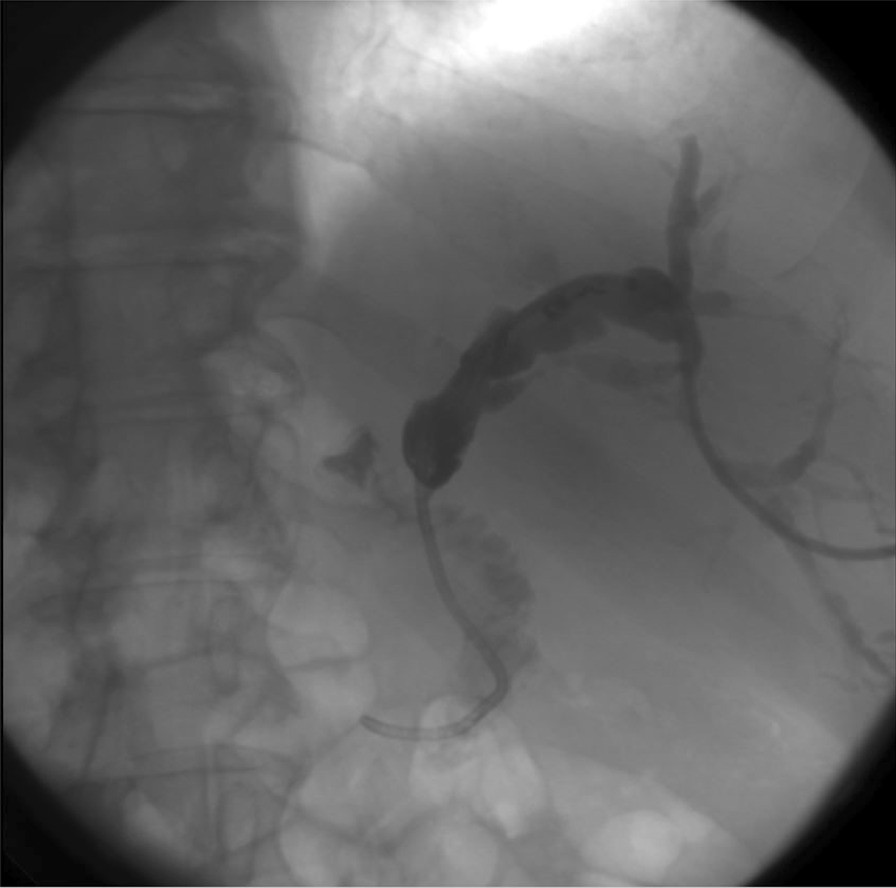

Fig. 8

From: Double rarity: malignant masquerade biliary stricture in a situs inversus totalis patient

PTD-cholangiogram: The suspicion of Bismuth-Corlette stage II Klatskin tumour arose because a subocclusive stenosis of the extrahepatic bile duct was proven